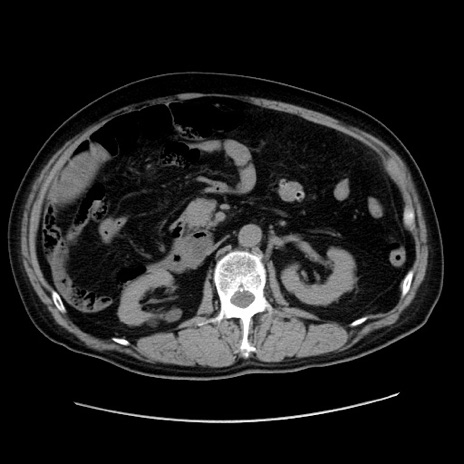

冠状断像

症例30(横断像)

【症例】80歳代男性

【現病歴】約6時間前から臍下部痛が出現。次第に腹部膨隆・背部痛も生じてきたため来院。背部痛の場所は変化しない。

【身体所見】意識清明、BT 36.3℃、BP  131/87mmHg、P 87bpm、SpO2 100%(RA)、臍周囲自発痛・圧痛あり、反跳痛なし、自発痛部位に一致して板状硬あり、腹部膨隆、腸雑音減弱、CVA tenderness両側陰性。